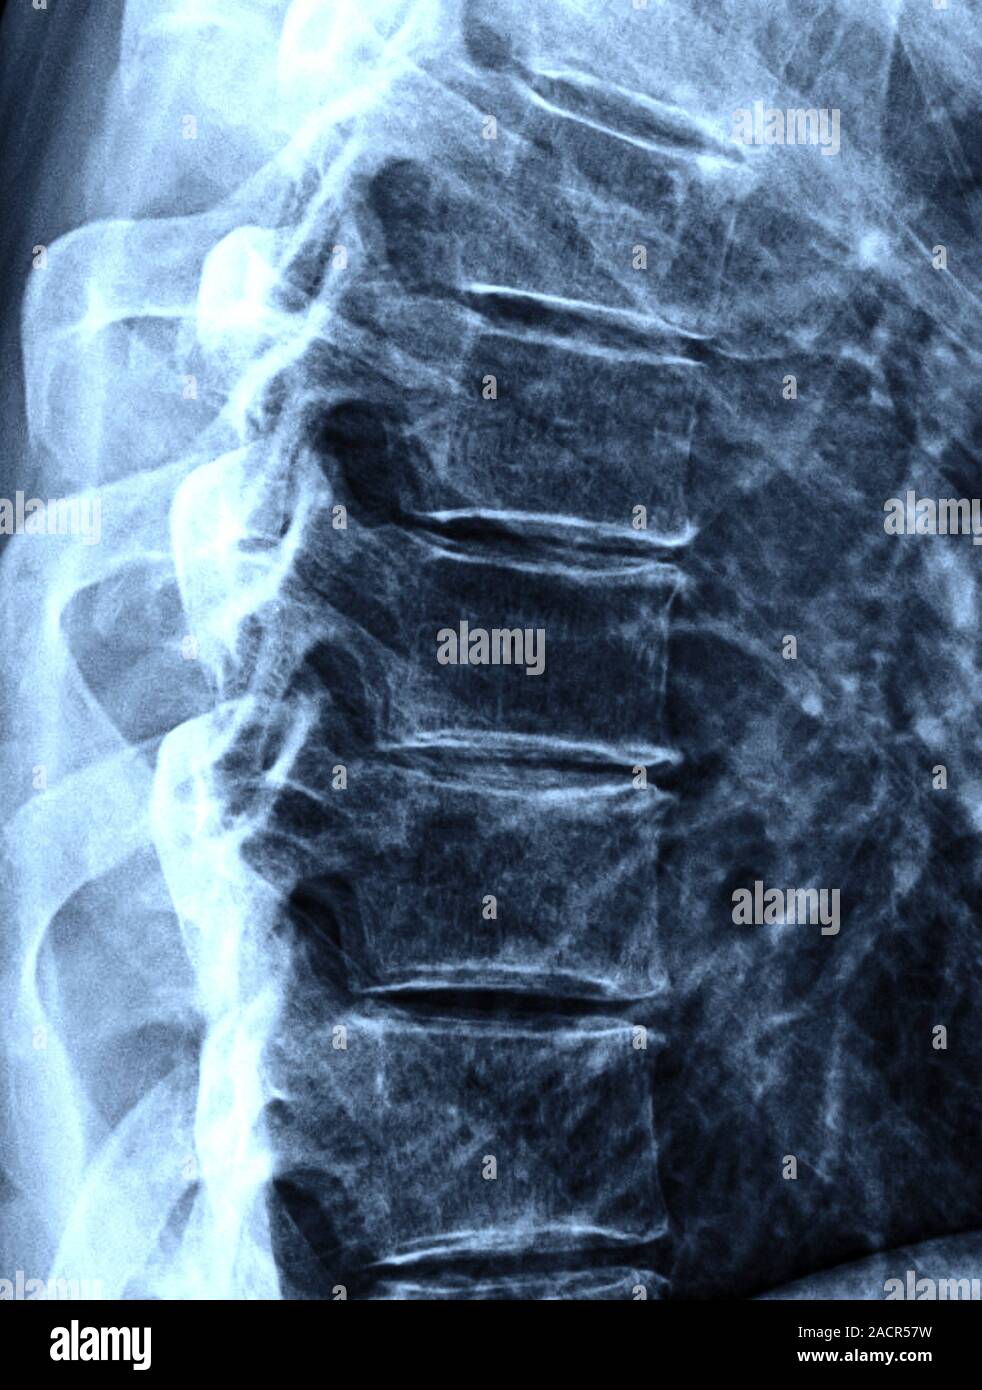

Arthritis of the back, Xray Stock Image M110/0498 Science Photo Arthritis Back Spine Find out how to diagnose, manage and prevent. Lumbar arthritis is a common condition that affects the lower back and causes pain, stiffness, and reduced mobility. Spinal arthritis is inflammation of the joints in the spine or pelvis that can cause pain and stiffness. It can be caused by osteoarthritis, psoriatic arthritis, reactive arthritis, or enteropathic arthritis. Learn about the. Arthritis Back Spine.

From www.sciencephoto.com

Osteoarthritis of the spine, Xray Stock Image C002/9621 Science Arthritis Back Spine Lumbar arthritis is a common condition that affects the lower back and causes pain, stiffness, and reduced mobility. Lumbar arthritis is a term for arthritis pain in the lower back. It can cause pain, stiffness, and loss of flexibility in the back. It can cause pain, stiffness,. Learn about the causes, symptoms, diagnosis and treatment of spinal osteoarthritis, a common. Arthritis Back Spine.

From www.alamy.com

Osteoarthritis. Xray of the thorarcic spine of a 64 year old man with Arthritis Back Spine Lumbar arthritis is a common condition that affects the lower back and causes pain, stiffness, and reduced mobility. Spinal arthritis is inflammation of the joints in the spine or pelvis that can cause pain and stiffness. Learn about the types, causes and risk factors of. It can be caused by osteoarthritis, psoriatic arthritis, reactive arthritis, or enteropathic arthritis. It can. Arthritis Back Spine.